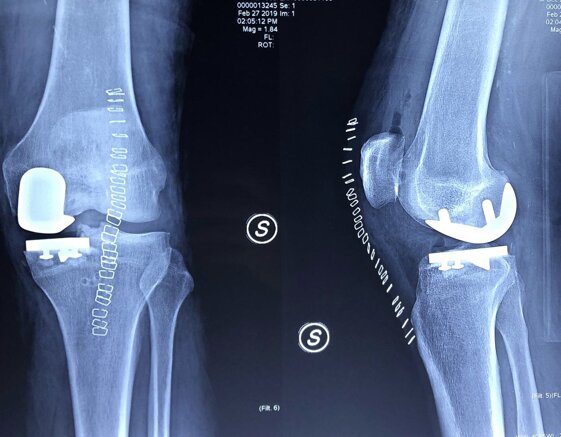

Radiografie post-operatorie in AP e LL di intervento chirurgico di artroprotesi cementata di ginocchio in pz donna con sovrappeso. In questo caso è stata utilizzata una protesi postero-stabilizzata (PS) con sacrificio quindi del legamento crociato posteriore (LCP)

Radiografie post-operatorie in AP e LL di intervento chirurgico di artroprotesi cementata di ginocchio. In questo caso è stata utilizzata una protesi a conservazione del LCP (CR) della stessa marca della protesi precedente